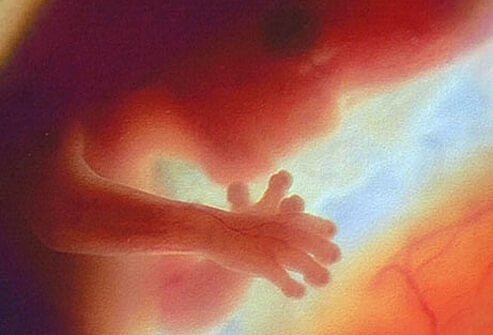

• Seventh Month

Seventh Month

At the beginning of the seventh month, the baby weighs about 1 ½ pounds and is about 14-16 inches long. His/her body is well-formed. Fingernails cover the fingertips.